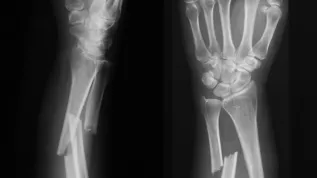

Prof. Sylwia Rodziewicz-Motowidło podkreśliła, że starzenie się społeczeństwa oraz choroby cywilizacyjne takie jak np. osteoporoza czy nowotwory sprawiają, że liczba pacjentów cierpiących z powodu złamań i chorób kości wciąż się zwiększa.

Jak podaje UG, wynalazek naukowców znajdzie zastosowanie w ortopedii, chirurgii szczękowo-twarzowej, neurochirurgii, a także w operacjach wykonywanych po urazach kości. W skład biomateriałów wchodzą: chitozan – naturalny polimer o wysokiej biokompatybilności, bioaktywne szkło i peptydy. Nowatorskie kompozyty mają także właściwości antybakteryjne i pro-regeneracyjne, co wpływa na przyspieszenie procesu gojenia i zmniejsza liczbę powikłań pooperacyjnych w chirurgii oraz mikrochirurgii. Biomateriały zostały tak opracowane, aby dodatkowo hamować rozwój szkodliwych drobnoustrojów, takich jak Staphylococcus aureus czy Pseudomonas aeruginosa.

Zespół opracował 20 różnych biokompozytów – z czego trzy zostały przebadane na zwierzętach. Opracowany biomateriał ma prosty skład, a przy tym wyjątkowe właściwości biologiczne – wspiera napływ komórek kości, mineralizację i odbudowę tkanki kostnej, a jednocześnie ulega biodegradacji i zostaje zastąpiony przez nowo powstałą kość. Dodatkowo materiał jest elastyczny i może być docięty przez chirurga bezpośrednio podczas operacji, co ułatwia jego zastosowanie kliniczne.